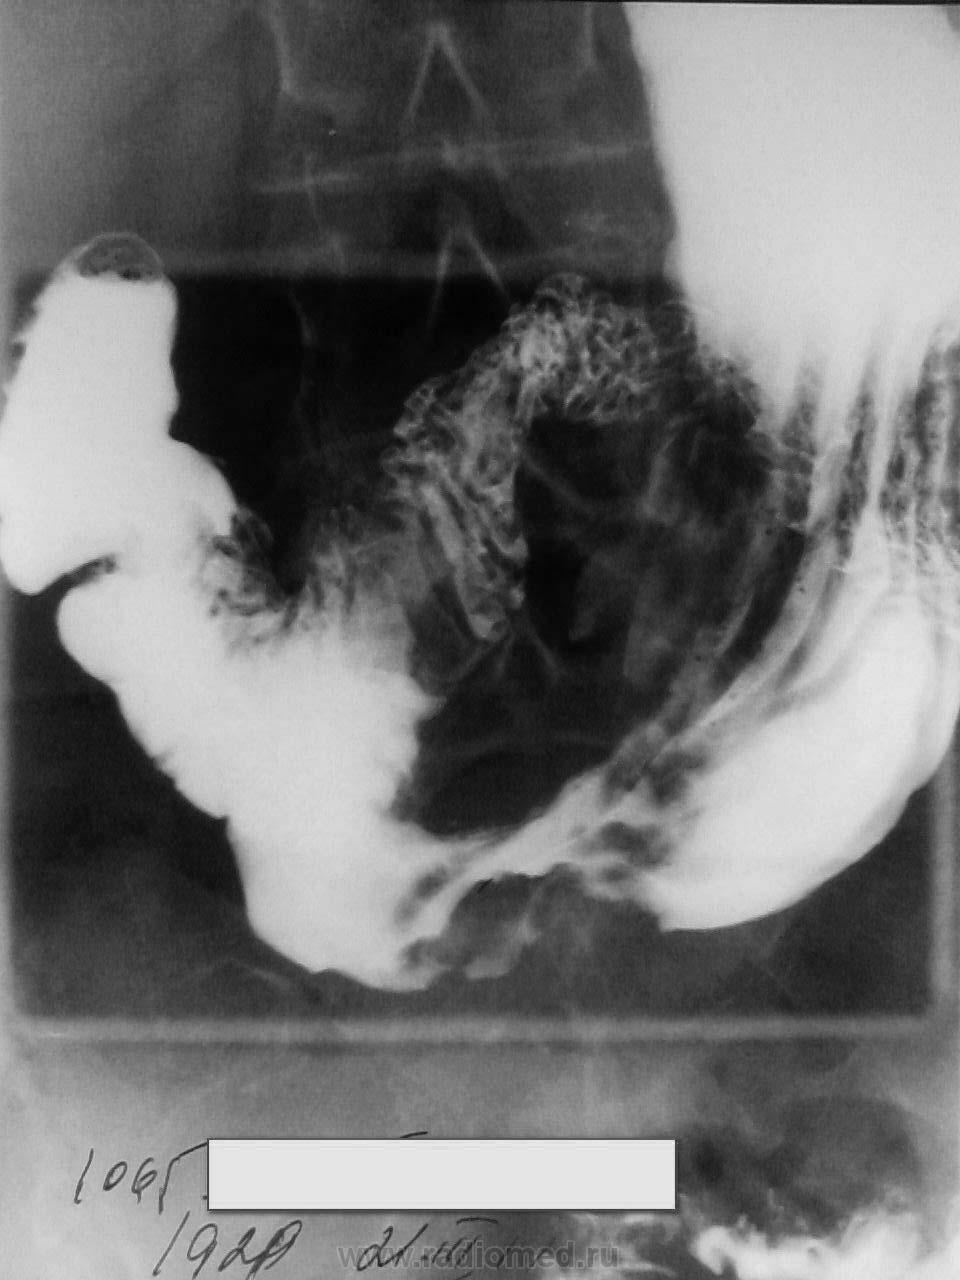

Деформация части 12-ти перстной кишки, скорее всего рубцовая

Аномалия ДПК. Ретрогастральное положение.

девект наполнения по большой кривизне в антральном отделе, на серии снимков, вроде присутствует, рельеф слизистой деформирован. ЭГДС делали?

рак наверное!

Думаю, да.

По малой кривизне перистальтика прослеживалась, а по большой - застывшая картина.

На мой взгляд, за что - это понятно. За неровность контура. Контур желудка при тугом заполнении барием должен быть ровным. А перистальтическая волна не может быть маленького размера (0,5 - 1,0 см). У меня вопрос был: где конкретно на снимках наиболее вероятен симптом ниши язвы, найденной на ФГС. Так как увиденная мной ниша на первом снимке бесследно исчезла на последнем снимке, я прошу помочь мне разобраться. Если сочтете нужным, конечно, коллеги. (Опыт по желудкам у меня небольшой).

[/quote]Дмирий, как это ни печально, но ниши я не нашла, хоть и очень старалась. Может, она фибрином прикрыта.

так там стенка инфильтрирована, основные изменения по большой кривизне просто.

на первом снимке нет тугого наполнения, поэтому это может и не ниша, на последнем я бы сказал депо конраста есть, просто на контур не всегда возможно вывести